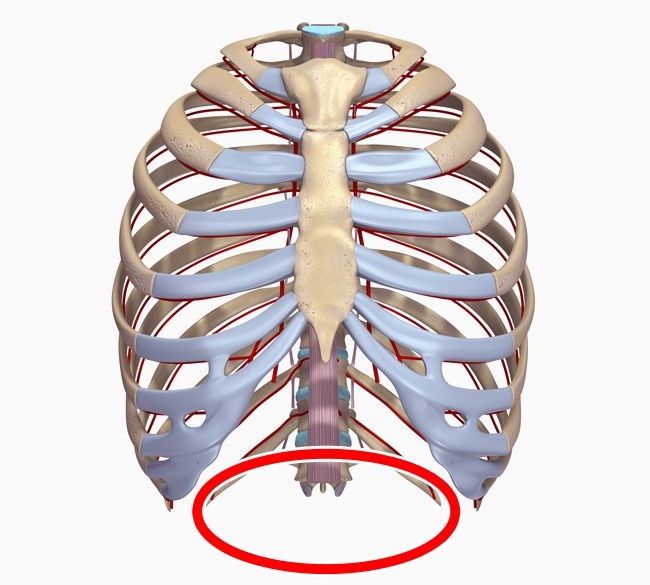

10. Thirteenth rib

Our closest cousins, chimpanzees and gorillas, have an extra set of ribs. Most of us have 12, but 8% of adults have an extra one.